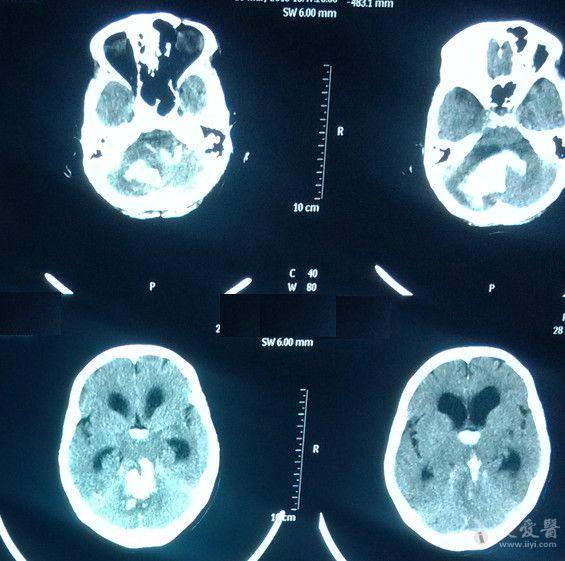

两例小脑出血并破入脑室,四脑室铸型,请教. - 神经外科专业讨论版 -

图片尺寸565x561